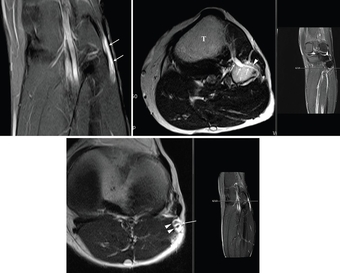

▲'신경내 결절종'(화살표 부분) MRI 영상 검사 사진

허리에서 시작하여 엉덩이 뒤쪽을 지나 다리 뒤편 허벅지, 종아리를 따라 발까지 내려가는 우리 몸에서 가장 크고 굵은 신경 다발인 좌골신경에서 발생한 희귀 난치성 양성종양 '신경내 결절종'(화살표 부분) MRI 영상 검사 사진